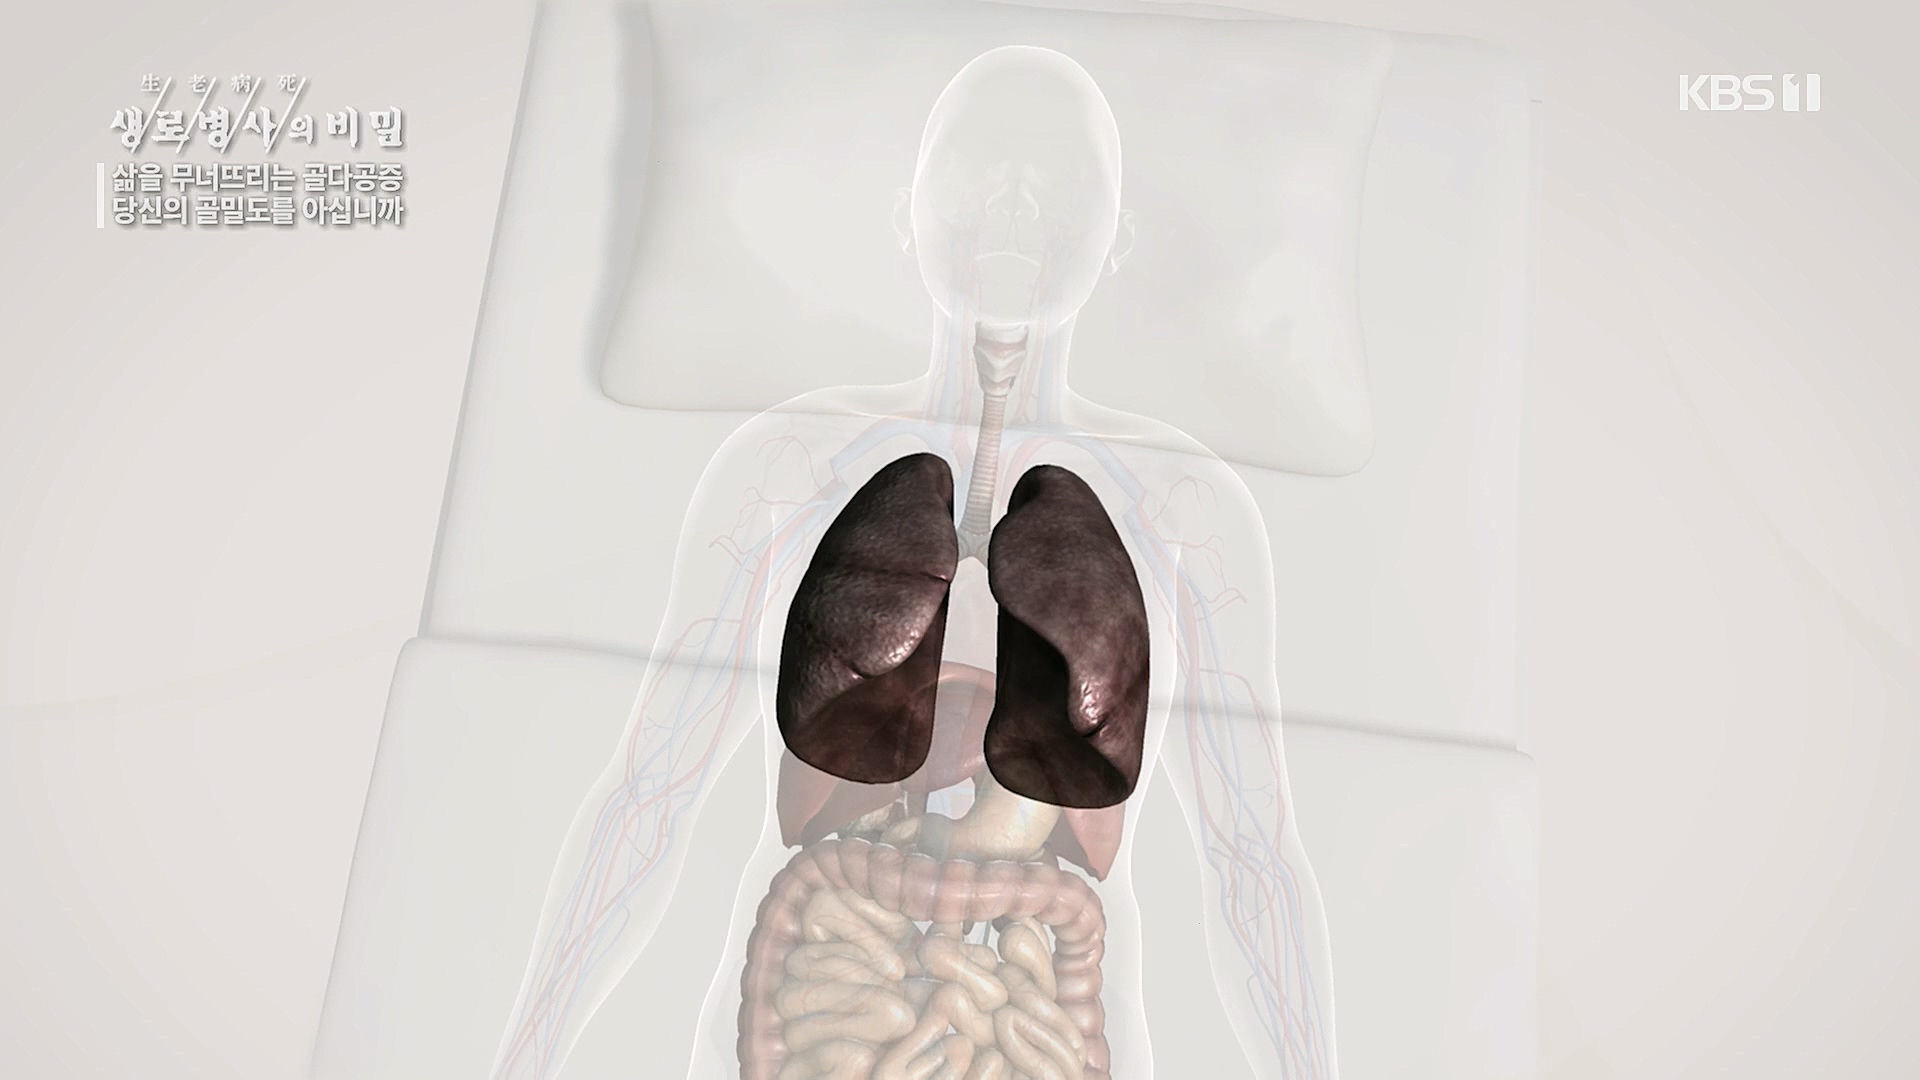

흡연